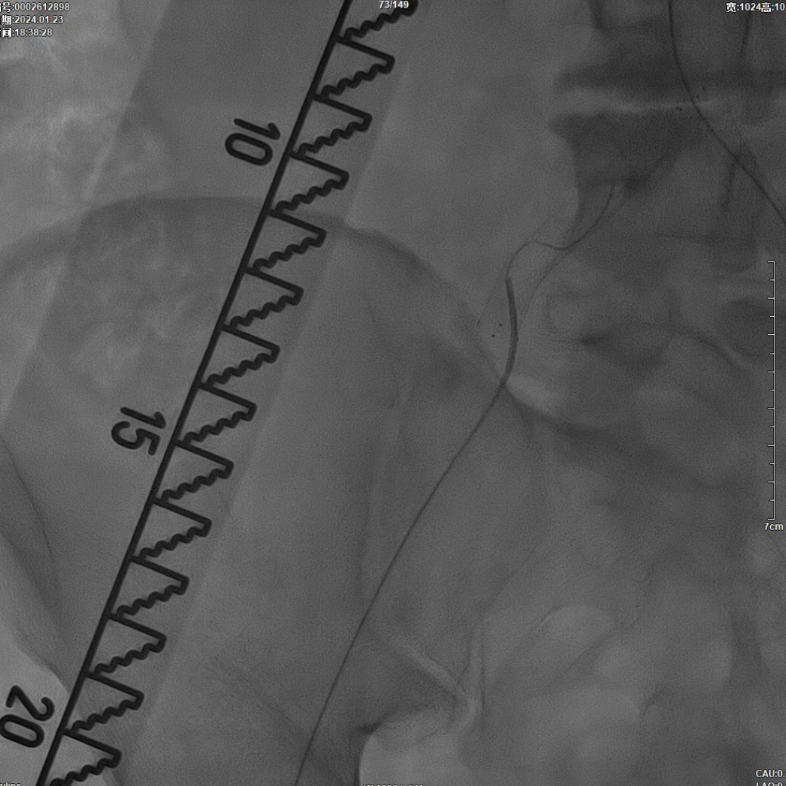

减容后造影显示仍存在重度残存狭窄,遂沿右侧股动脉置入VBX支架(直径11mm,长度59mm)。支架定位需满足近端完全覆盖腹主动脉病变段,远端距离双侧髂总动脉分叉至少1.5cm,以避免后扩张时大球囊对髂动脉造成损伤。

该图解释为何远端距离双侧髂总动脉分叉至少1.5cm,以避免后扩张时大球囊对髂动脉造成损伤。

CERAB技术的关键点一:经双侧股总动脉植入2枚VBX球囊扩张式覆膜支架(8L×79mm),与腹主动脉覆膜支架腔内平行放置,且两枚支架端平齐对接。